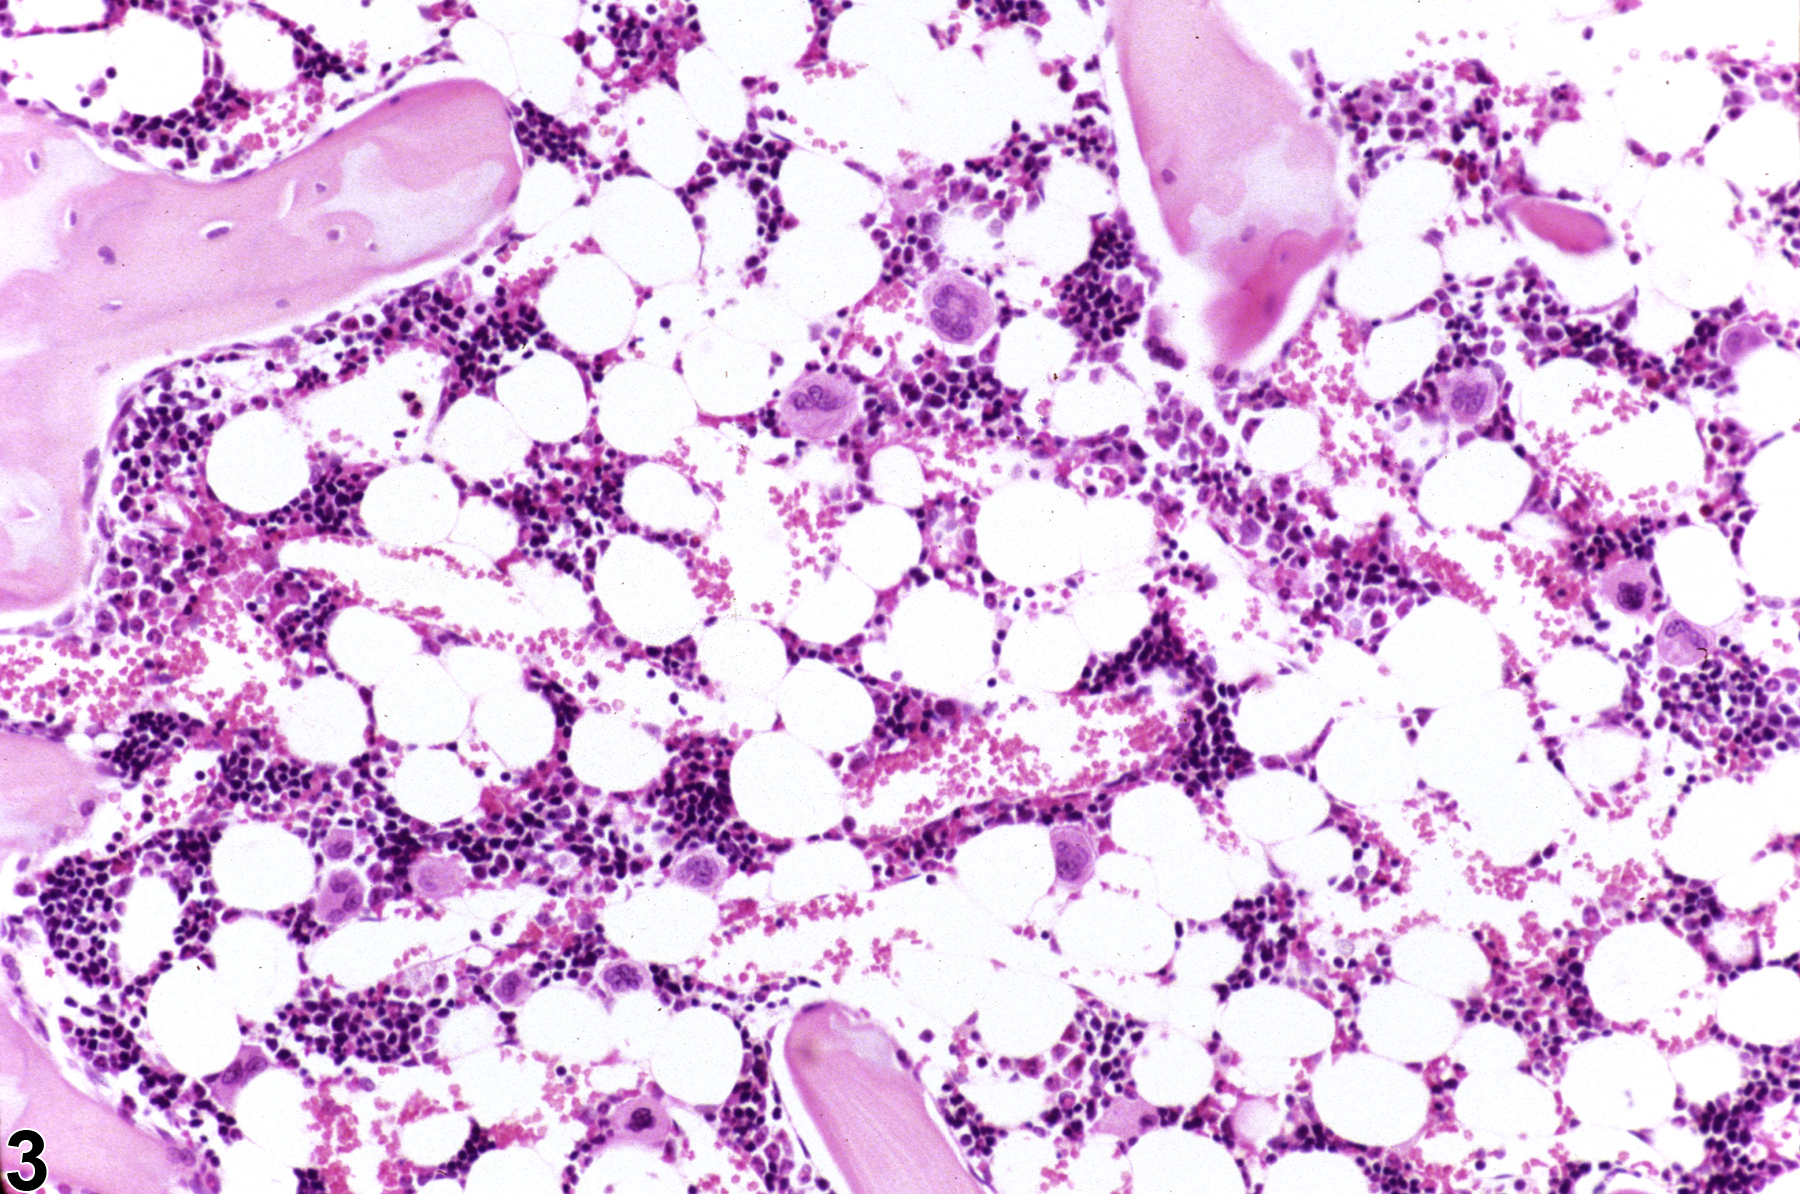

Changes in bone marrow cellularity may involve all or individual cell lines. Changes in the erythroid or myeloid cell lines may shift the M:E ratio relative to controls. Normal M:E ratios of rats and mice are reported between 0.80 and 2.79, with an average of 1.5, and are dependent on strain and age, stressing the importance of comparing treated animals with concurrent controls. Histologic sections allow for a rough estimate of the M:E ratio to aid in the evaluation of cellularity, while cytologic preparations are needed for a more precise determination of the M:E ratio and evaluation of subtle changes in synchrony of maturation.

Hypercellularity of the bone marrow is recorded in treated animals when there is an increase in hematopoietic cells relative to adipocytes compared with concurrent controls (Figure 2, Figure 4, and Figure 5). Hypercellularity may occur as a nonspecific or direct (e.g., with cytokine administration) response to compound administration but more commonly is due to a regenerative response as a consequence of decreases in peripheral blood cells, recovery from a xenobiotic-induced bone marrow injury, or inflammation. For example, hypercellularity may be secondary to sepsis or a result of blood loss, hemolytic anemia or platelet consumption/destruction. Stimulation to produce more of one cell line can cause increased production of other cell lines, causing an overall increase in bone marrow cellularity. With marked hypercellularity, hematopoietic cells may fill the entire marrow space, even extending through the nutrient foramina.

Bone marrow in a control female F344 rat from a subchronic study.